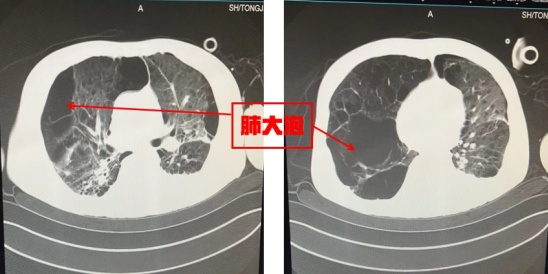

老周拥有一个“千疮百孔”的肺。15年前,老周被诊断了“肺结核”,经过1年左右的规律抗结核治疗,终于控制住了。没成想,5年前再次被诊断“支气管扩张伴咯血”,到同济大学附属同济医院呼吸与危重症医学科住院治疗。虽然咯血控制了,但是发现肺功能严重受损,需要长期随访治疗,老周几乎每半月就要去呼吸与危重症医学科门诊就诊1次。在医生和女儿的劝说下,老周终于下决心把抽了40年的烟也戒掉了,决心要保养好自己身体。

唯一令人头疼的事情就是老周的肺部情况,虽然呼吸机支持力度已经逐渐下调,但此次的肺损伤对于本就严重功能减退的肺部而言,无疑是雪上加霜,使得恢复之路更加艰难而漫长。考虑到老周肺部情况,重症医学科经过全科讨论,对其进行了“气管切开术”,并联系康复医学中心的医师为老周开始了一系列的肺康复治疗。经过近一个月的治疗,老周逐渐清醒,并顺利脱离呼吸机,并且转出监护室继续康复治疗。